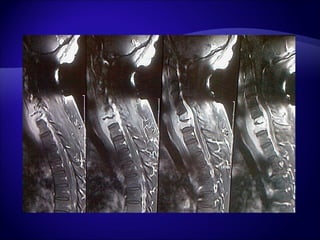

IRM en urgence :  - Compression de la moelle cervicale, recul du mur postérieur. - Images compatibles avec des métastases sur 3 étages

IRM en urgence: - Compression de la moelle cervicale, recul du mur postérieur. - Images compatibles avec des métastases sur 3 étages